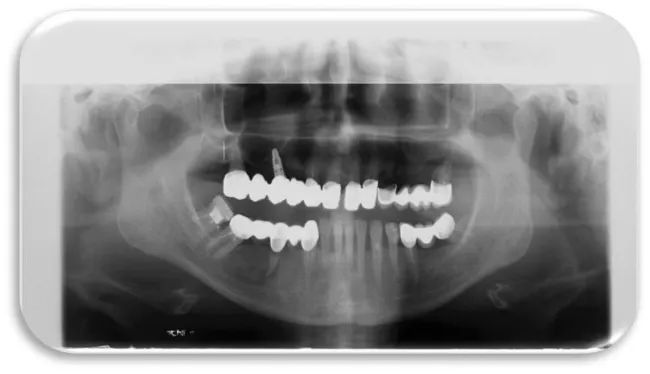

The first patient was at the age of 48 with male gender and generally with good health. There are no contraindications to make oral surgery. The patient is not allergic to any medication. A dental implant was placed 12 months ago (Figures 11,12), the dental implant’s position was 46. The implant was 4.1 mm in diameter and 12 mm in length. The patient has peri-implantitis, a RTG intraoral radiography image was recorded and marginal bone resorption was observed. The depth of the gingival sulcus was 10mm. Dehiscencia was seen in the patient from the buccal side of the implant (Figure 13). The bone defect was closed with a bone graft (Figures 14-16).

Woman at aged 37 year age, in good health condition and without any systemic diseases, allergic to penicillin came for prosthetic rehabilitation. She was without second premolar and first molar in the lower right quadrant. The patient was provided with dental implants at 45 and 46 (Figures 17-19). After a month on a 45-implant, retrograde peri-implantitis appeared. In chronological order, X-ray images are shown on figures from 17 to 20.

Different treatment strategies were performed in order to remove peri-implantitis. Provided treatment include: debridement of bone tissue, use of bone grafts from known biocompatible grafting materials, i.e. BioOS, disinfection of the surface of the dental implant. After 12 months, another radiography record was made, where ceramic crowns over the implants were seen and there was no longer peri-implantitis (Figure 20) [19,20].